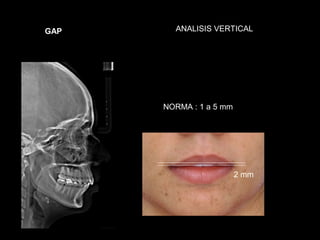

GAP     ANALISIS VERTICAL

NORMA : 1 a 5 mm

2 mm